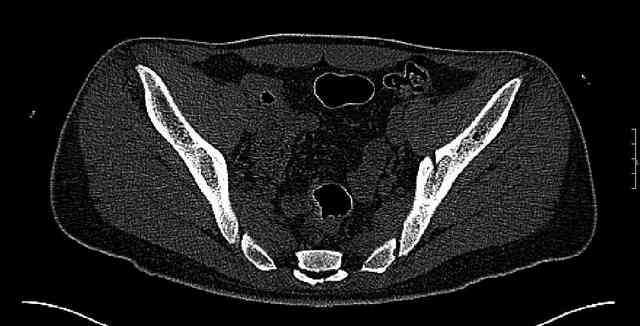

Some more images. Does it help to guess which part of the acetabulum is displaced?

Normal appearing SI joints and a healed posterior column limb... my bet's on caudal segment displacement.

The anterior element of the fracture is so low and the anterior roof arc angle must be at least 60 deg.

The posterior element is so minmally undisplaced. There is good congruence of the joint, and to top it all, 6 weeks have passed. If you consider ORIF now, I don't expect that much improvement could be accomplished. Not to mention the need for extensive approaches with their morbidity.